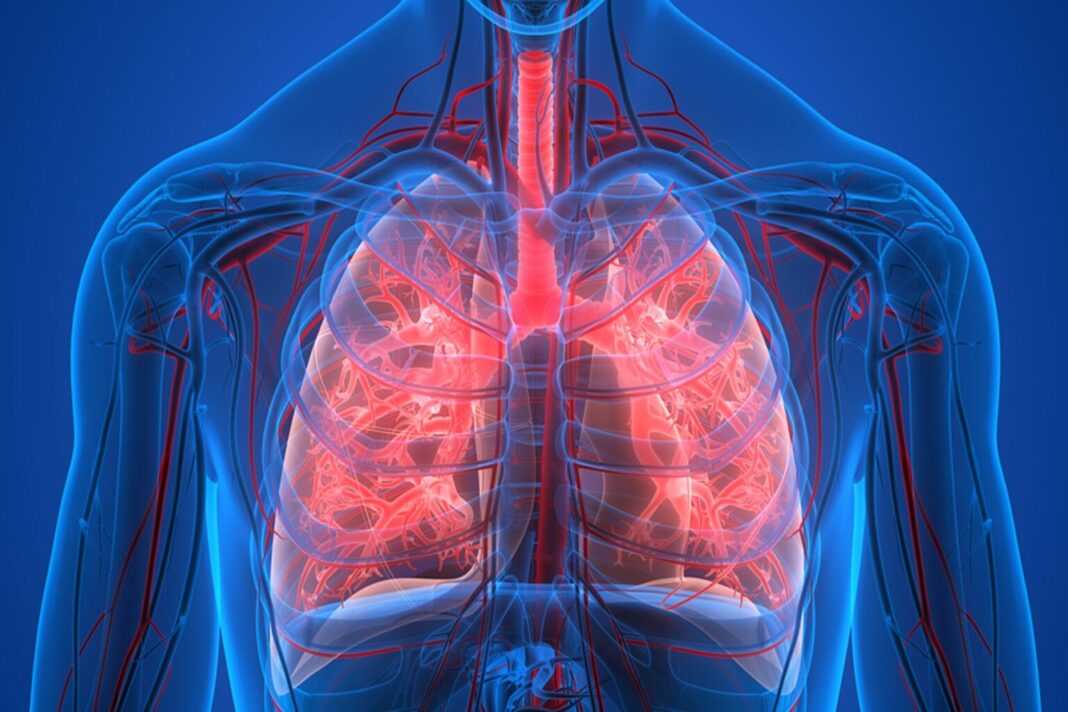

Η πνευμονική αρτηριακή υπέρταση (ΠΑΥ) είναι ένας τύπος υψηλής αρτηριακής πίεσης στους πνεύμονες, κατά την οποία τα αιμοφόρα αγγεία στενεύουν, αποφράσσονται ή καταστρέφονται, αναγκάζοντας την καρδιά να εργάζεται πιο σκληρά και, με τον καιρό, οδηγεί σε καρδιακή αδυναμία και ανεπάρκεια. Η ασθένεια είναι σχετικά σπάνια, αλλά επηρεάζει περίπου 100.000 άτομα στις Ηνωμένες Πολιτείες και οδηγεί σε 20.000 θανάτους ετησίως. Δεν υπάρχει θεραπεία. Σε μια μελέτη που δημοσιεύτηκε στις 4 Μαΐου 2022 στο Science Translational Medicine, ερευνητές στο University of California San Diego School of Medicine περιγράφουν την υποκείμενη οδό σηματοδότησης που οδηγεί σε PAH—και μια νέα θεραπεία μονοκλωνικών αντισωμάτων που εμποδίζει τον ανώμαλο σχηματισμό αιμοφόρων αγγείων που χαρακτηρίζει την ασθένεια.

Σε κυτταρικό επίπεδο, η ΠΑΥ εξελίσσεται με τον πολλαπλασιασμό των αγγειακών λείων μυϊκών κυττάρων (vSMC) που προκαλούν στένωση των μικρών αρτηριών στους πνεύμονες, οδηγώντας σε προοδευτικά λιγότερο οξυγόνο στο αίμα. Μια ερευνητική ομάδα, με επικεφαλής την ανώτερη συγγραφέα Patricia A. Thistlethwaite, MD, Ph.D., καθηγήτρια χειρουργικής στο UC San Diego School of Medicine και καρδιοθωρακοχειρουργό στο UC San Diego Health, εστίασε στην υπερέκφραση του συνδέτη NOTCH JAGGED- 1, μια πρωτεΐνη δέσμευσης που εμπλέκεται στη σηματοδότηση των κυττάρων και, στην περίπτωση αυτή, στην ανάπτυξη μικρών πνευμονικών vSMCs.